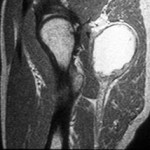

The proper diagnosis of nerve pain in hip starts with obtaining the health history of the patient. The doctor will also be asking questions about the onset of the pain and the triggers that worsen it; onset of fever; presence of diarrhea; and hurting in the abdomen or other joints. Physical examination will also be done. Then, imaging tests such as X-rays, CT scan, bone scan, and magnetic resonance imaging (MRI). Blood tests that include lymphocyte count, ESR (erythrocyte sedimentation rate) and CRP (C-reactive protein) are done to confirm nerve pain in hip.